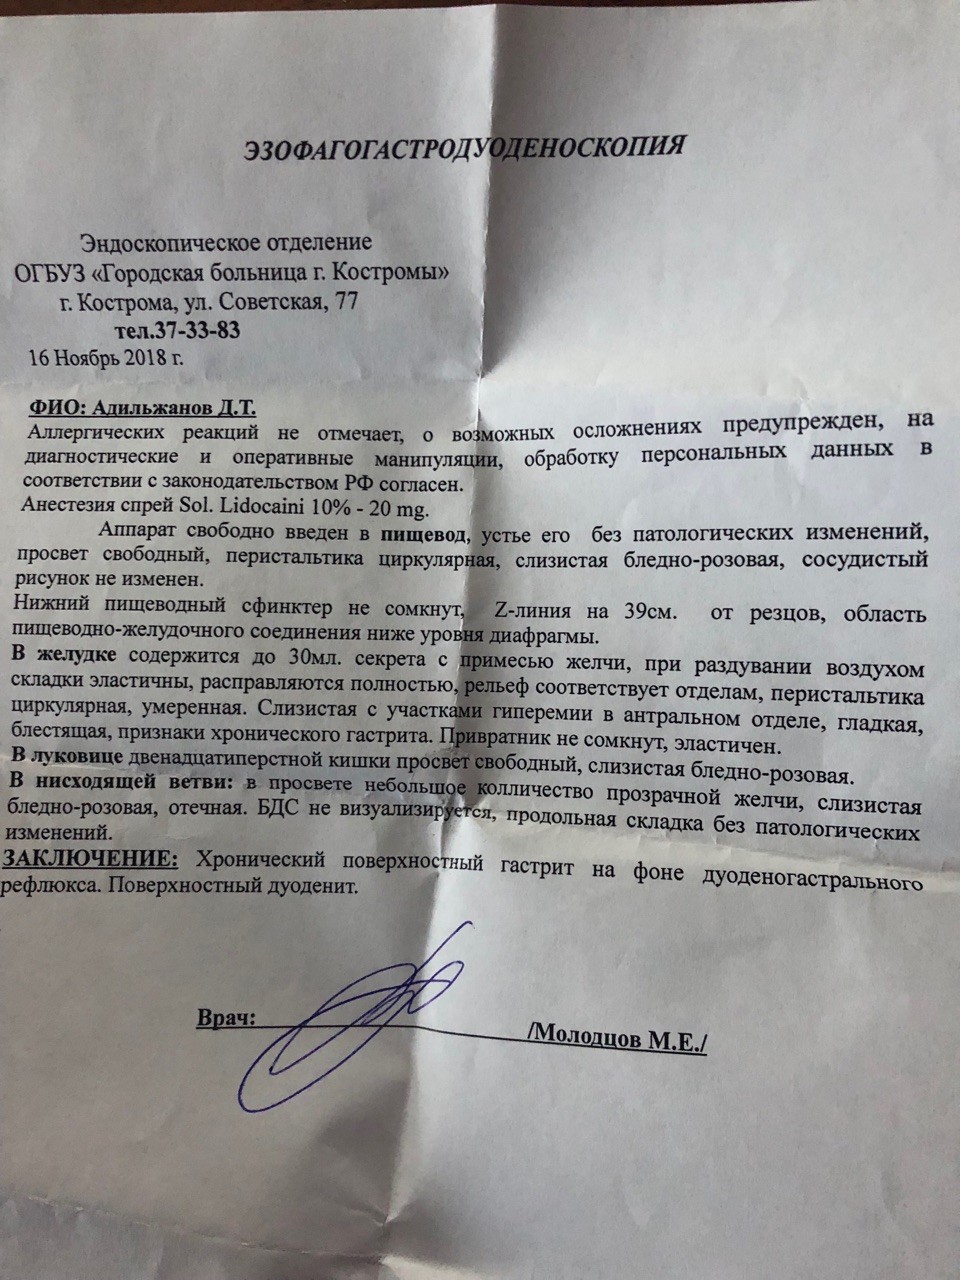

Информация и фотографии о хроническом гастрите и дуодените

Раздел: Фотодневник открытий